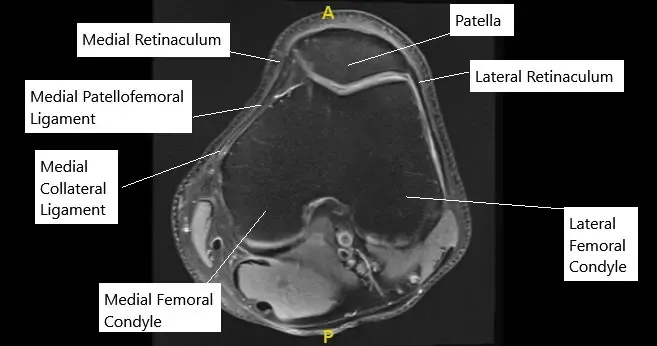

La rótula se sitúa en una pequeña ranura en la parte delantera del fémur. A medida que la rodilla se dobla, la rótula se mueve arriba y abajo por este surco. El ligamento patelofemoral medial, situado en la parte interna de la rodilla, actúa como una correa para evitar que la rótula se desplace hacia afuera. Cuando este ligamento se rompe, la rótula puede desplazarse fuera de su lugar.

La resonancia magnética de rodilla en la sección axial mostró un MPFL normal.